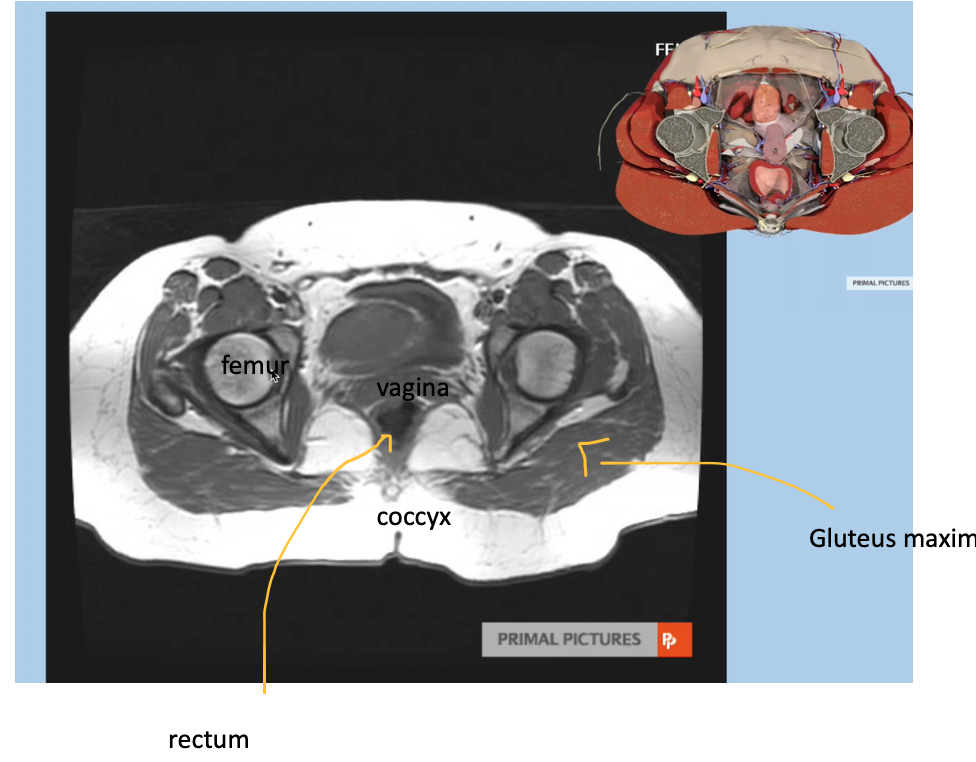

Axial female MRI, pelvis